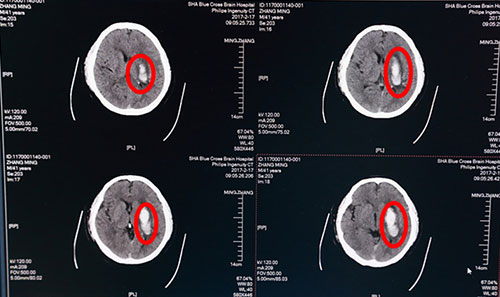

2月17日,張先生來藍十字腦科就診,并慕名找到李振并主任。此時距患者發(fā)病已6天,急查頭顱CT示:1.左側(cè)基底節(jié)區(qū)腦出血(急性期),部分蛛網(wǎng)膜下腔滲出;2.腦干、雙側(cè)基底節(jié)區(qū)腔隙灶,初步診斷為:高血壓腦出血,運動性失語,肺部感染,高血壓病III級(很高危),高血壓性心臟病,II級糖尿病?紤]到患者病情不容耽擱,保守治療效果不佳,兩次出血35ML,有再出血可能,手術(shù)指征明確,征求家屬意見后,遂決定緊急為張先生實施“顱內(nèi)血腫微創(chuàng)清除術(shù)”進行治療。

術(shù)前頭顱CT:紅圈內(nèi)白色部分為腦出血血腫

當(dāng)日,李振并主任急診在局麻下為張先生施行了“顱內(nèi)血腫微創(chuàng)清除術(shù)”。術(shù)中根據(jù)頭顱CT片三維定位,取左側(cè)顳部為穿刺點,用一次性血腫穿刺針直達血腫中心,接引流管,抽出暗紅色血塊40多ML。